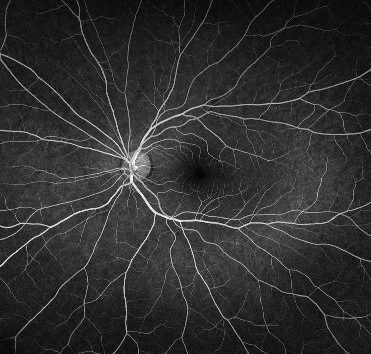

What is Macular Eye Disease?

Macular disease affects the very centre of your vision and can have a profound effect on your vision. The most common causes of macular disease are Age Related Macular Degeneration and Diabetes. Dr Sharwood delivers the latest treatments with care and compassion throughout your journey to preserve and optimise your vision

To reduce fluid leakage and/or bleeding at the macula caused by age related macular degeneration, diabetic macular disease or vein occlusions. The injections will improve or maintain your existing vision and reduce the risk of future blindness.